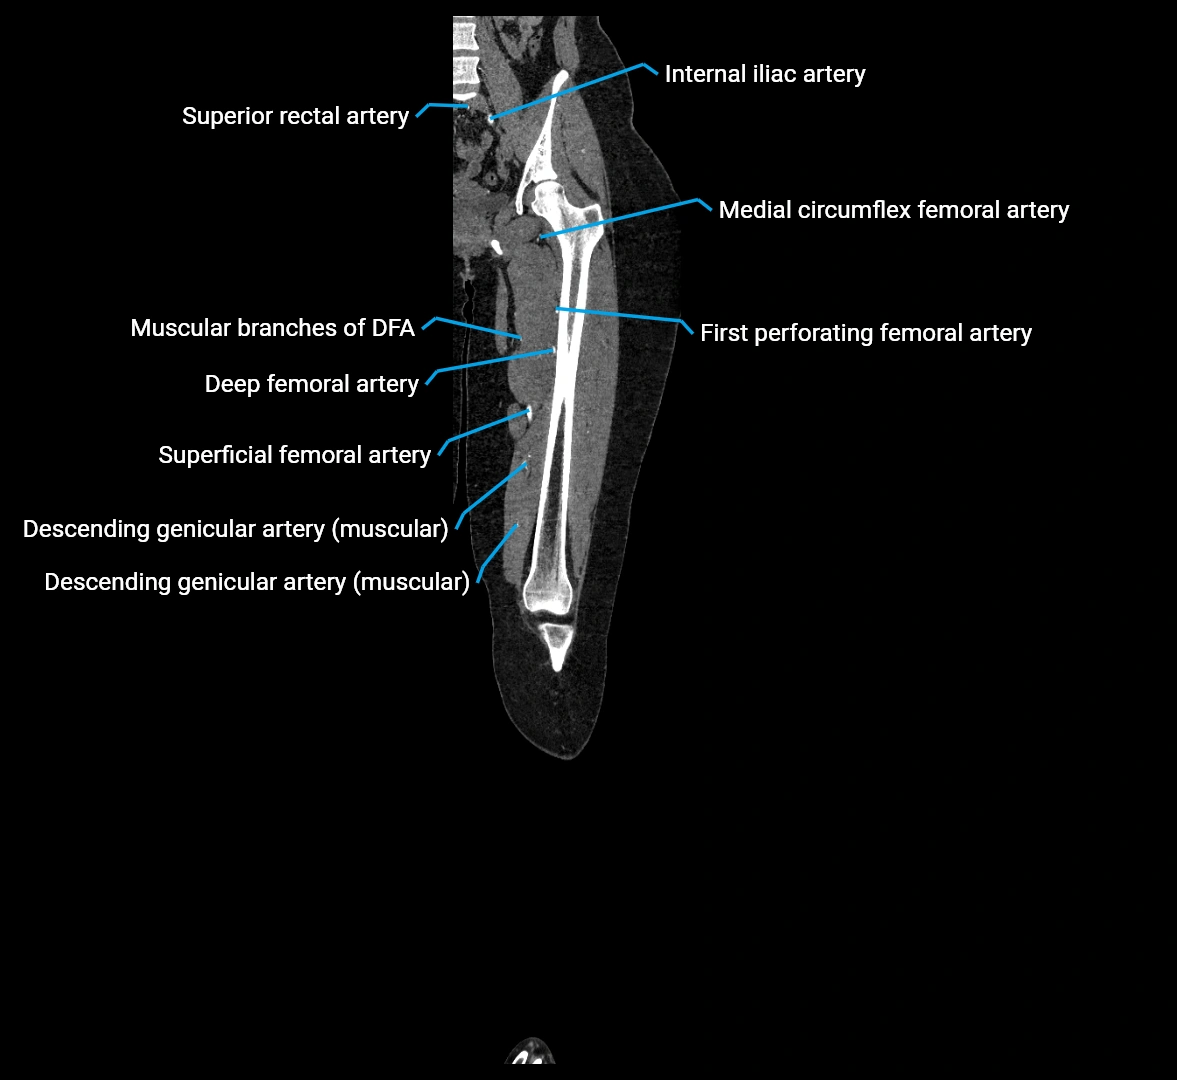

CT images

image